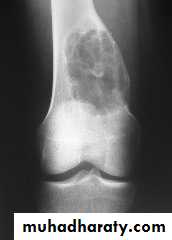

O/E vague swelling at the bone end and signs of joint irritation.X-ray:

Rarefied area of the bone end reaching just below the articular surface.Eccentric lesion with bone expansion and ballooning with cortical thinning, sometimes pathological fracture.

There may be calcific trabiculations inside the lesion giving it the commonly known saop-bubble appearance.